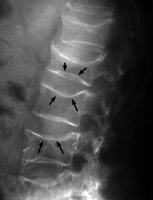

Originally coined for the changes of senile osteoporosis, biconcave deformities of the vertebral bodies ("fish vertebrae") are characteristic of disorders in which there is diffuse weakening of the bone. The name is derived from the actual appearance of a fish vertebrae which normally has depressions in the superior and inferior surfaces of each vertebral body. This sign is typically used for osteopenia.

Lateral L-spine - Click on the image for a larger version